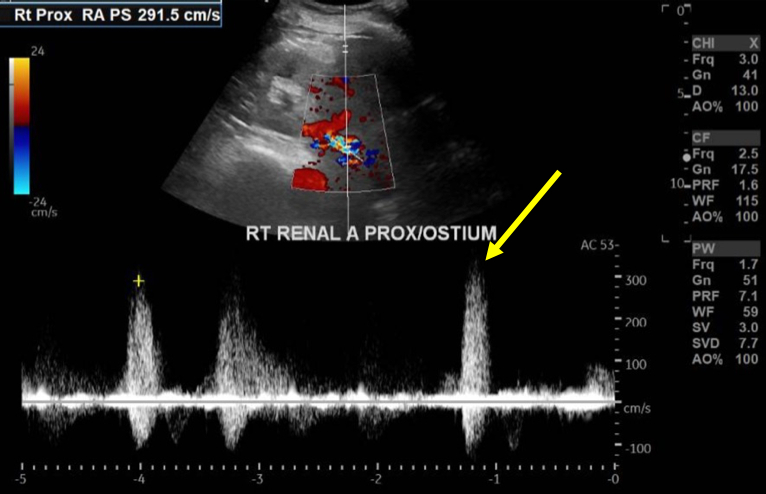

The patient was initially treated with non-invasive ventilation, a continuous nitroglycerin infusion, and IV furosemide with rapid improvement in her symptoms and vital signs. She was quickly transitioned to simple nasal cannula and oral antihypertensive medications; IV diuresis was continued. However, despite these initial improvements, her renal function steadily worsened over the subsequent days. Renal doppler ultrasound revealed an elevated right renal artery peak systolic velocity of 292 cm/sec with delayed acceleration times. After an interdisciplinary discussion, she underwent right renal artery angiography and drug-eluting stent placement.

Post-procedural renal doppler ultrasound showed an improvement in right-sided PSV to 137 cm/sec with no evidence of RAS. Post-discharge blood pressures remained improved and her renal injury resolved with no further hospitalizations after six months.